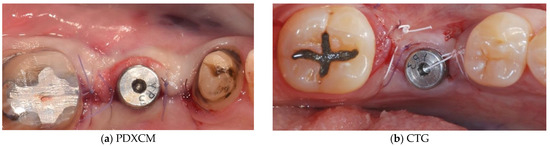

| Papi et al. [27] | 12 patients | Prospective cohort study | 12 months | N R | PDXCM: 1.25 |

| Zafiropoulos et al. [38] | 27 patients | Prospective, randomized examiner-blinded controlled clinical study | 6 months | N R | PDXCM: 1.06 |

| Stefanini et al. [39] | 10 patients | Case series | 12 months | PDXCM 0.65 ± 0.41 | PDXCM: 1.2 ± 0.18 |

| Papi and Pompa 12 [40] | 12 patients | Prospective pilot cohort study | 12 months | PDXCM: 4.32 | N R |

| Schmitt et al. [41] | 14 patients | Controlled clinical trial | 6 months | N R | PDXCM: 0.30 ± 0.16 |

| Verardi et al. [42] | 24 patients 24 implants | Prospective study | 6 months | PDXCM 1.33 ± 0.71 | N R |